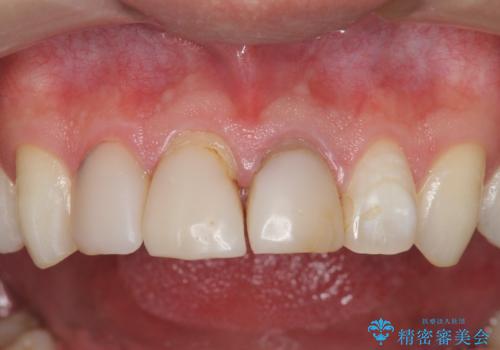

前歯の変色 審美性の改善

- 前歯の変色や形態を含む、見た目を改善したいと希望され来院されました。

視診・X線検査・歯周組織検査より下記のような問題が列挙され、長期的な予後を見込むために一つづつ問題の解決を計ります。

・不十分な根管治療 →マイクロスコープを用いる精密根管医療

・歯の変色 →ジルコニアクラウンの製作

・歯肉縁下カリエス →部分矯正による歯の挺出・歯周外科